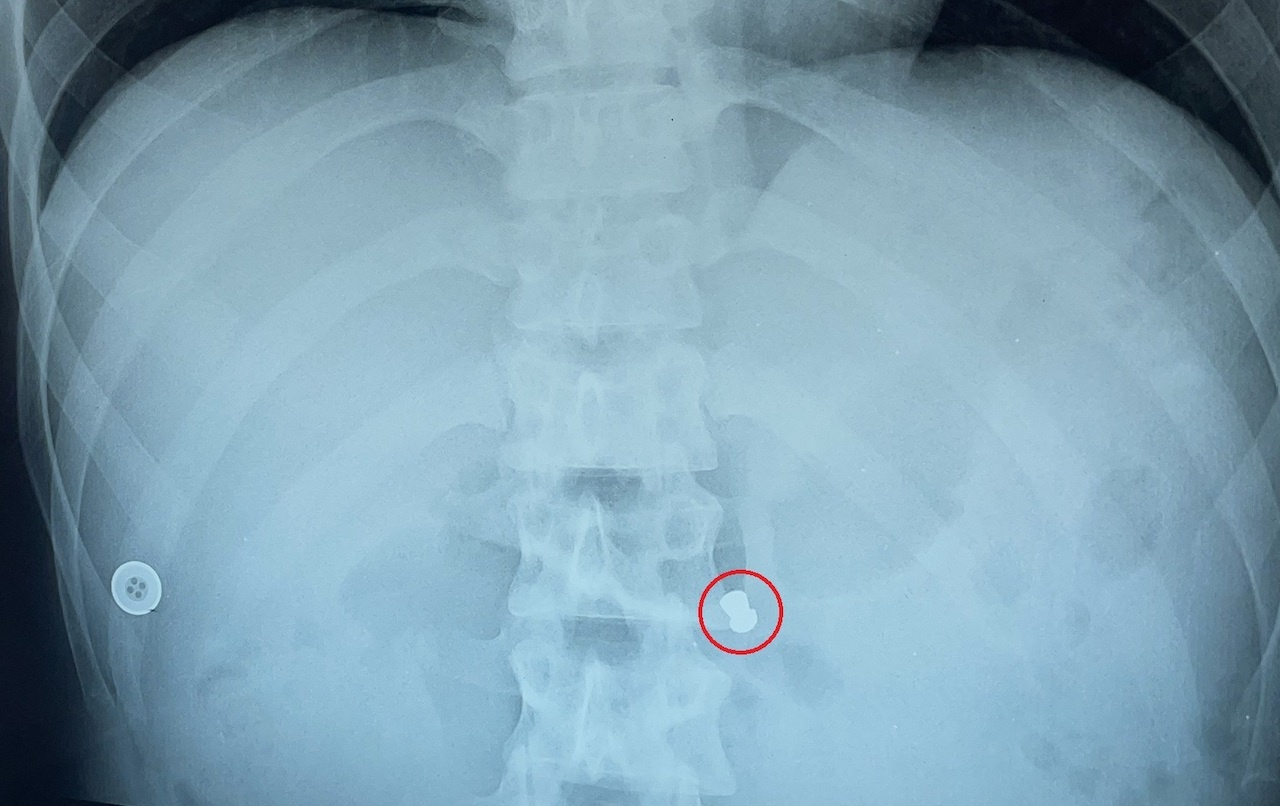

Sau lần nội soi để tán sỏi 9 năm trước, người phụ nữ ở Đồng Tháp không quay lại bệnh viện để rút ống dẫn lưu niệu quản nên thường xuyên bị đau hạ vị.